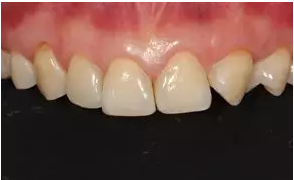

術后上前牙正面照

病例分享|復合樹脂微創(chuàng)美學修復關閉上前牙間隙